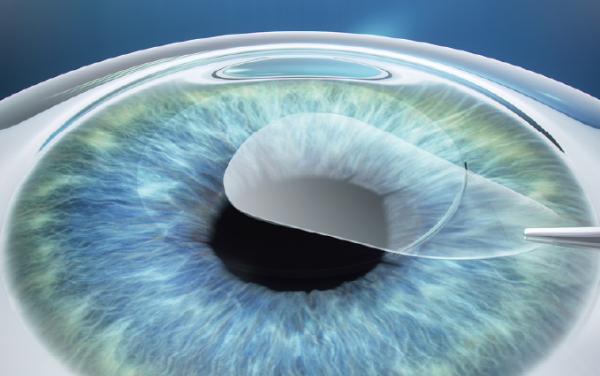

SMILE(Small Incision Lenticule Extraction)は、ドイツのCarl Zeiss 社が開発した次世代近視矯正レーザー手術です。SMILEはアメリカ・ヨーロッパ・アジアを中心に80か国以上で11,000,000件以上の実績があります。この手術は、角膜に2~3mm程度の小さな切開を加え、内部のレンチクル(円盤状の角膜組織)を取り除くことで視力を矯正します。これにより、自然な角膜構造を保ちながら、痛みや合併症のリスクを最小限に抑えることが可能になりました。従来のLASIK手術に比べて角膜への侵襲が少なく、ドライアイのリスクも軽減するとされています。

レンチクルの形成

フェムトセカンドレーザーを使用し、

角膜の内部に微細なレンチクルを

形成します。

小切開の作成

約2~4mmの小さな切開を

角膜表面に作成します。

レンチクルの摘出

作成した切開部からレンチクルを丁寧に取り出します。これにより角膜の屈折力が変化し、視力が矯正されます。

自然治癒を待つ

縫合も不要で、

切開部は自然に癒合します。